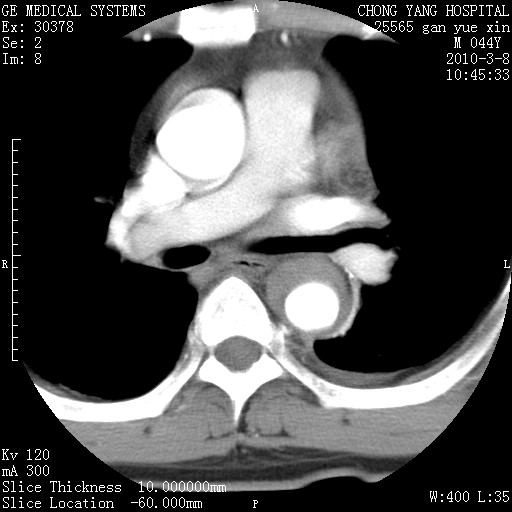

标题: CT24940:主动脉增强,典型病例。 [打印本页]

标题: CT24940:主动脉增强,典型病例。

夹层动脉瘤。

动脉夹层

夹层动脉瘤,典型

主动脉夹层。

动脉夹层的分型:

⒈debakey分型:根据主动脉夹层累及部位,分为三型:ⅰ型:原发破口位于升主动脉或主动脉弓部,夹层累及升主动脉、主动脉弓部、胸主动脉、腹主动脉大部或全部,少数可累及髂动脉。ⅱ型:原发破口位于升主动脉,夹层累及升主动脉,少数可累及部分主动脉弓。ⅲ型:原发破口位于左锁骨下动脉开口远端,根据夹层累及范围又分为ⅲa,ⅲb。ⅲa型:夹层累及胸主动脉。ⅲb型:夹层累及升主动脉、腹主动脉大部或全部。少数可累及髂动脉。

⒉stanford分型:a型:夹层累及升主动脉,无论远端范围如何。b型:夹层累及左锁骨下动脉开口以远的降主动脉。

夹层动脉瘤,少量胸水

夹层动脉瘤;左侧少量胸腔积液。

典型主动脉夹层。